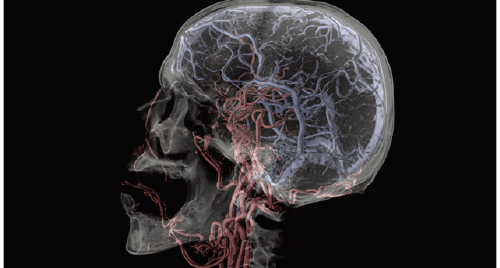

SYNAPSE 3D’s advanced image analysis technology aids clinical interpretation, reporting, and treatment planning. Especially,

automatic organ segmentation technology enables fast and effective workflow, powered by REiLI, FUJIFILM's AI brand. With

a series of high-tech applications developed in collaboration with clinical specialists, SYNAPSE 3D quickly and accurately

delivers imaging result that promotes effective care collaboration.

Based on the previously stored information, the areas recognized as blood vessels are extracted.

Cerebral Arteries and Vein separation